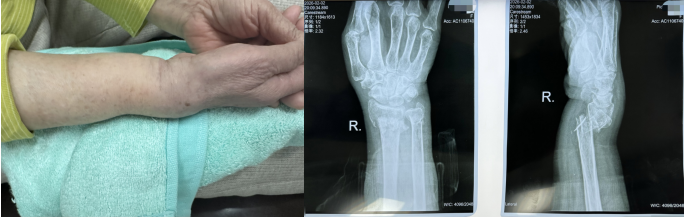

阳光讯(记者 郑亚雷 通讯员 曾雪琴)近日,82岁的姚奶奶在家中行走时不慎跌倒,右手撑地后即感右腕部剧烈疼痛、明显肿胀伴畸形,活动完全受限。家属紧急将姚奶奶送至当地医院就诊,X线检查显示为右腕部粉碎性骨折并伴有移位。因病情复杂,当地医院建议转诊治疗。当晚,姚奶奶在家属陪同下来到西安市红会医院手法复位室,薛安邦主治医师第一时间接诊,并迅速启动诊疗流程。

接诊后,薛安邦主治医师详细询问病史、认真查体,并结合影像学资料,明确诊断为右尺桡骨远端粉碎性骨折伴移位。影像显示,骨折端严重粉碎、移位显著,且累及关节面,属高难度、高风险类型,治疗难度极大。更为棘手的是,患者年逾八旬,身体机能衰退,合并多种基础疾病,若选择手术治疗,麻醉及围术期风险极高。因此,保守治疗成为更优选择,但对复位技术提出了更高要求。

方案确定后,在董博主任的指导下,薛安邦与周健副主任医师默契协作,凭借精湛娴熟的手法技艺和丰富的临床经验,轻柔稳健地将移位的骨折碎片逐一精准复位。整个过程流畅有序,力道把控恰到好处。复位后复查X线显示,骨折端达到功能对位。董博主任表示,考虑到患者高龄不耐受强刺激,先以功能复位为核心,后期可通过加垫调整逐步优化复位效果。